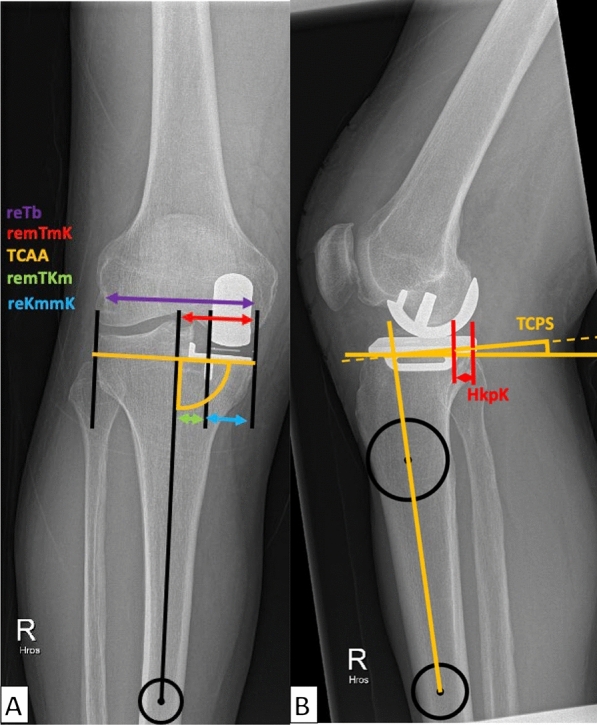

Methods: A total of 2063 patients with medial UKA using the Oxford® mobile partial knee implant were analyzed between July 2014 and September 2022. Various preoperative and postoperative radiographic parameters determining pre- and postoperative alignment and implant positioning, incidence and characteristics of periprosthetic fractures, and patient demographics were assessed. Statistical analyses, including Mann-Whitney U test and logistic regression, were conducted to identify significant associations and predictors of tibial fractures.

Results: Of the 1853 cases that were finally included in the study, 19 (1%) patients experienced TPF. The fracture group presented with a significantly shorter relative mediolateral and posteroanterior distance between the keel and cortex [mediolateral: 23.3% (23.2-24.8%) versus 27.1% (25.7-28.3%), p < 0.001; posteroanterior: 8.4% (6.3-10.3%) versus 10.0% (9.8-10.1%), p = 0.004]. Additionally, an increased posterior tibial slope in pre- and postoperative radiographs [preoperative: 10.4° (8.6-11.1°) versus 7.7° (5.4-10.0°), p < 0.001; postoperative 9.1° ± 3.1° versus 7.5° (5.9-9.0°), p = 0.030] was observed in the fracture group. Furthermore, the use of smaller-sized implants (AA) was associated with higher fracture rates (p < 0.001). Anatomical variants, such as a medial overhanging tibial plateau, were not observed.

Conclusions: In UKA, type Oxford TPF are linked to shorter mediolateral and posteroanterior keel-cortex distances, increased pre- and postoperative PTS, and small implant sizes (AA). Fracture lines often extend from the distal keel to the medial tibial cortex. These findings emphasize the importance of precise implant positioning and sizing to minimize fracture risk. Level of evidence Retrospective single-center study, III.